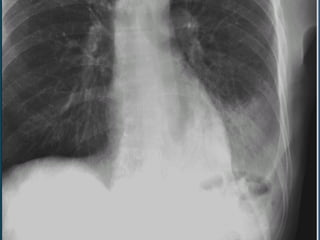

Infiltrado parahiliar bilateral difuso de tipo nodular que abarca ambos lóbulos inferiores. Aumento del perfil derecho e izquierdo del corazón Sobredistensión pulmonar